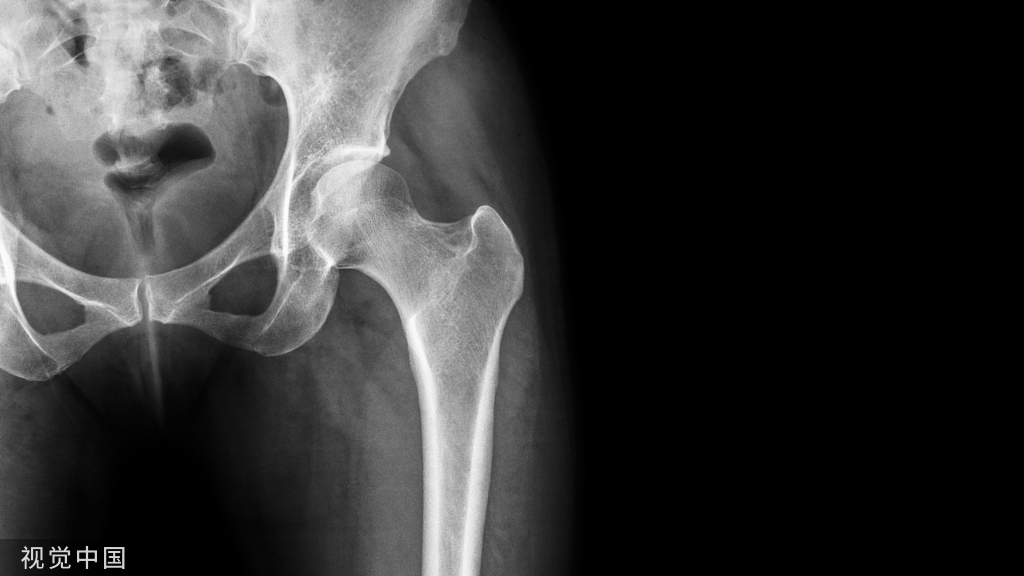

股骨远端及胫骨近端截骨的最终目标是允许假体能矫正外翻畸形,但不可过度矫形,使内侧间室和外侧副韧带应力过大,这样可能会导致内侧间室的过度磨损。

按胫骨为先的原则,使用髓外力线杆进行胫骨截骨,并允许胫骨假体植入。由于外侧间室有更大活动度,外侧间室应比内侧间室单髁关节置换的屈伸间隙稍大些。冠状面上,应与胫骨机械轴线相匹配;矢状面上应有一定后倾。然后进行矢状面垂直截骨,锯片垂直于截骨模块。此次截骨应沿股骨外侧髁的内缘,轻微内旋,以适应股骨和胫骨完全伸直时由于“锁-扣”机制导致的旋转。小心操作,避免损伤前交叉韧带胫骨附着点。垂直截骨锯片可留在原处防止损伤前交叉韧带胫骨附着点,标准截骨锯片配合截骨模块完成胫骨水平截骨。胫骨截骨骨块可辅助确定胫骨假体大小。由于外侧胫骨平台的形态特点,外侧间室胫骨截骨块比内侧间室要偏短、偏宽。

通过特殊器械进行股骨远端截骨以获取屈伸间隙平衡。股骨远端和后髁截骨对调整关节间隙非常重要,尤其是股骨远端。完成屈曲间隙测量,伸直间隙应能保证放入同样大小的试模。

与内侧间室单髁关节置换相比,外侧间室单髁关节置换要感觉稍松些。通常采用胫骨截骨面系统辅助进行平衡伸直力线。股骨远端截骨完成后,应用“二合一”截骨模块进行股骨后髁截骨,截后方斜面,去除后方骨赘及残余半月板。选择合适大小的股骨试模,大小以能覆盖截骨面为宜,前方不宜超出很多,因为其会增加髌骨与假体关节面不匹配的风险。同样方法测量胫骨假体大小,并放入试模。屈伸膝关节应自然,无松弛或太紧。分别在完全伸直位、屈曲30°、中度屈曲、完全屈曲状态检查关节稳定性。矢状面上关节稳定性也很重要。检查膝关节的运动和稳定性时,应去除拉钩以保证韧带处于正常张力状态。